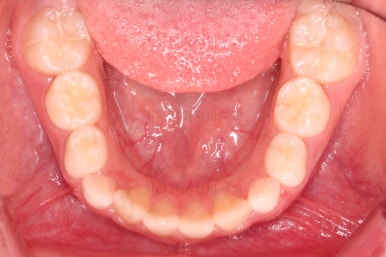

1. 초진

부산어린이교정 키다리아저씨치과에 처음 내원했을 당시의 입안의 모습입니다.

앞니가 거꾸로 물리는 전형적인 앵글씨 3급 부정교합 환아의 모습이었습니다.

아직 유치가 많이 남아 있었꼬, 아래 앞니는 4개가 영구치 맹출, 윗니는 2개가 영구치 맹출 상태였습니다.